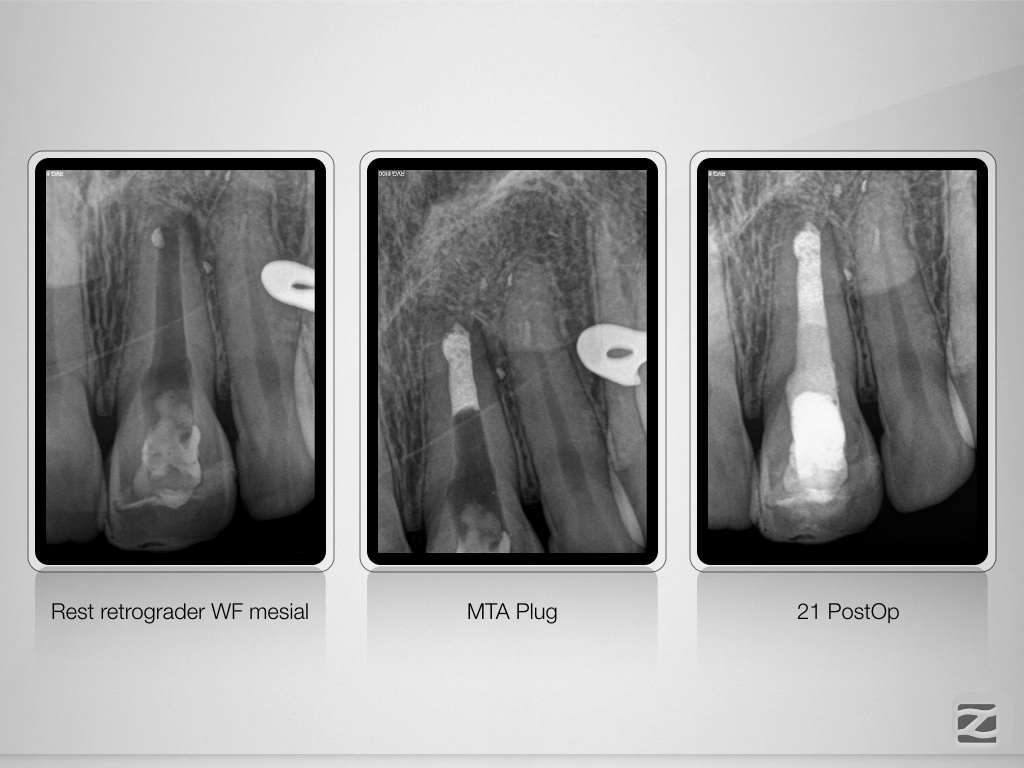

Letzte Möglichkeit WSR?